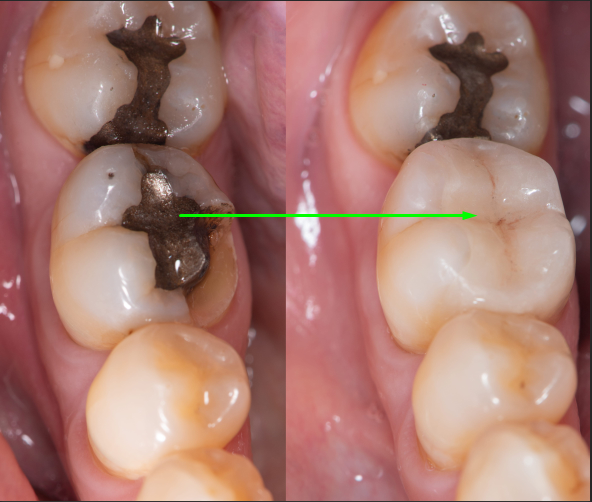

Tooth-colored dental fillings, also known as composite or white fillings, have revolutionized the world of dentistry by providing a seamless and aesthetically pleasing solution for repairing cavities and damaged teeth. Unlike traditional silver amalgam fillings, which are conspicuous due to their metallic appearance, tooth-colored fillings blend harmoniously with your natural teeth, making them virtually indistinguishable.

These composite fillings are composed of a mixture of fine glass particles and acrylic resin, meticulously color-matched to your tooth's shade. The result is a restoration that not only restores your tooth's strength and function but also enhances your smile's overall beauty.